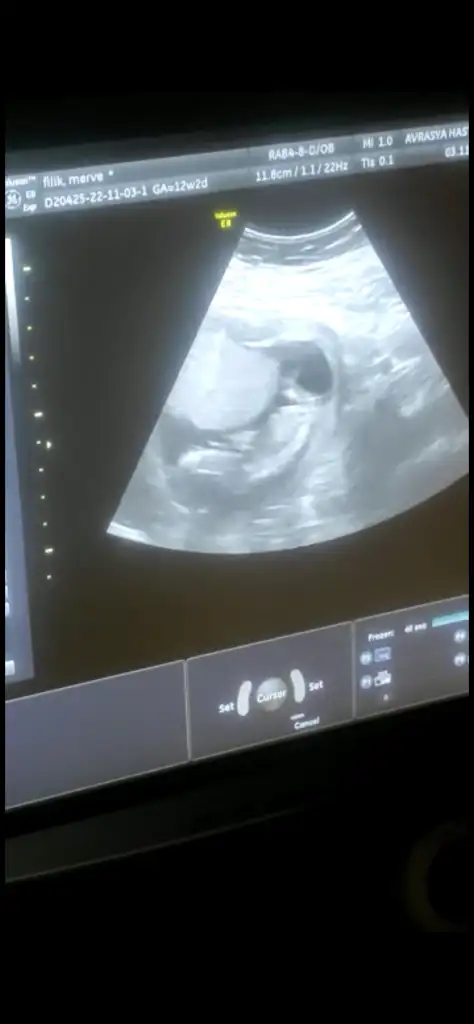

• IMG_20221026_094938.webp

IMG_20221026_094938.webp

24 KB · Görüntüleme: 46

• IMG_20221026_094924.webp

IMG_20221026_094924.webp

21,6 KB · Görüntüleme: 34

• IMG_20221026_094919.webp

IMG_20221026_094919.webp

32,2 KB · Görüntüleme: 39